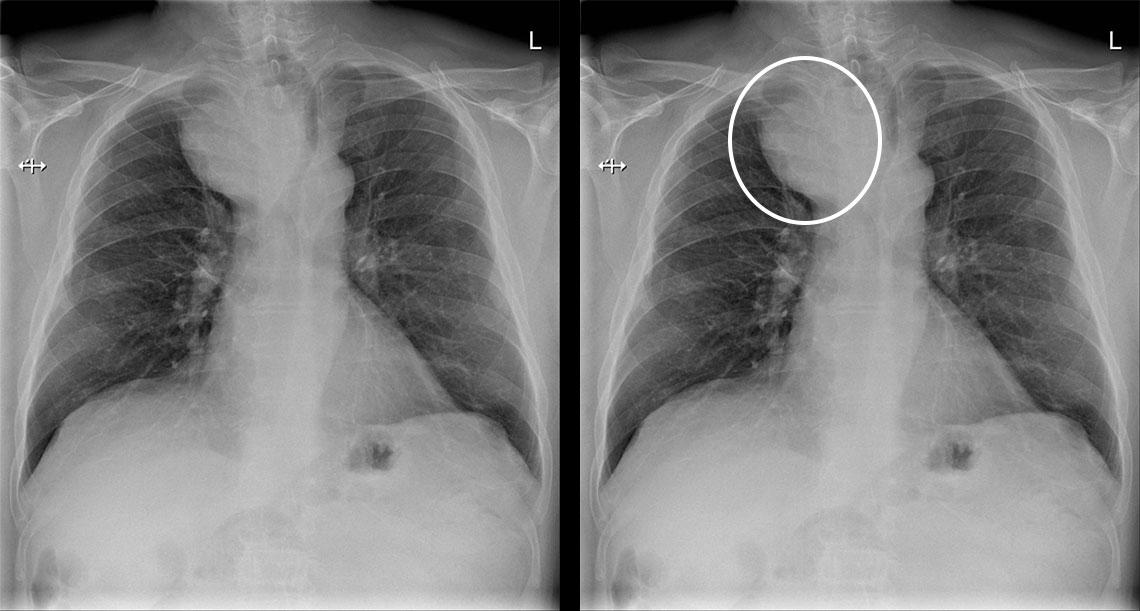

Kookas struumakyhmy keuhkokuvassa.

Potilaan keuhkokuva tarkistettiin pitkittyneen flunssan vuoksi. Oireita selittävää syytä ei löytynyt, mutta kuvassa näkyy ylämediastinumin massa, jonka vuoksi trakea devioi vasemmalle. Keuhkokudoksessa ei ole aktuellia ja hilusalueet sekä keuhkosopet ovat siistit. Kuvan löydös oli aihe jatkotutkimuksille. Ultraäänitutkimuksessa todettiin retrosternaalisesti ulottuva kookas oikea kilpirauhaslohko, joksi thoraxkuvan muutoskin sopii.